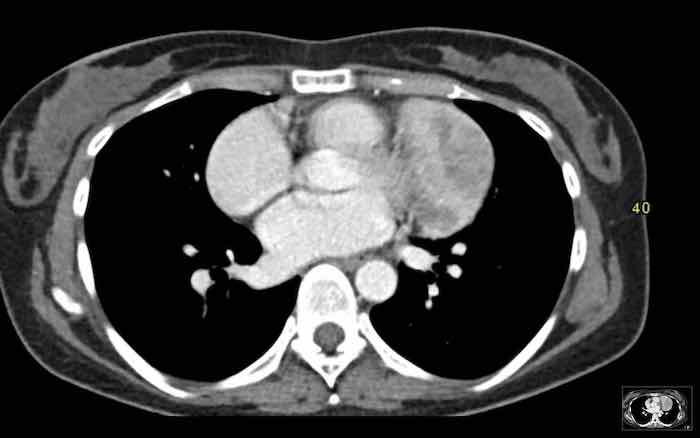

Các hình ảnh này của một bệnh nhân nam 43 tuổi có đau ngực.

Hình ảnh

Có một khối ở trung thất trước mạch máu.

Bờ không đều và tổn thương dương tính trên PET-CT.

Thảo luận

Chẩn đoán có khả năng nhất là thymoma, có thể là thể xâm lấn hoặc thậm chí là ung thư tuyến ức.

Tiếp tục xem phim chụp tiền phẫu hai tháng sau…

Hai tháng sau, một phim chụp tiền phẫu được thực hiện.

Rõ ràng là tổn thương đã nhỏ hơn.

Tuy nhiên, phẫu thuật viên vẫn quyết định cắt bỏ tổn thương và kết quả giải phẫu bệnh là ung thư tuyến ức.

Chúng tôi không có giải thích rõ ràng cho những gì đã xảy ra ở đây.

Có một số phản ứng trong mô mềm xung quanh khối u trên phim chụp đầu tiên (mũi tên).

Có thể đã có tình trạng viêm trong khối u và các mô xung quanh, khiến khối u trông lớn hơn.